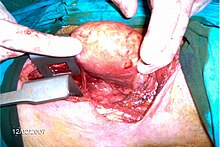

Vergrößerte Schilddrüse mit sicht- und tastbarem Knoten vor der Luftröhre

Der Situs bei einer Schilddrüsenoperation; der vergrößerte Schilddrüsenlappen wurde angehoben.

Der Situs im weiteren Verlauf; der vergrößerte Schilddrüsenlappen wird herauspräpariert, sichtbar die Ligaturen zur Blutstillung.

Als Struma (Kropf) wird jede Vergrößerung der Schilddrüse über ihr normales Volumen hinaus bezeichnet. Solche Vergrößerungen können objektiv mithilfe einer sonographischen Untersuchung der Schilddrüse festgestellt werden. Grundsätzlich kann jede der Schilddrüsenkrankheiten mit einer Volumenvergrößerung einhergehen. Die weitaus häufigste Ursache für eine Struma ist mit etwa 90 % der ernährungsbedingte Jodmangel (auch als blande Struma bezeichnet). Das Symptom der Struma war bereits in der Antike bekannt.[16]